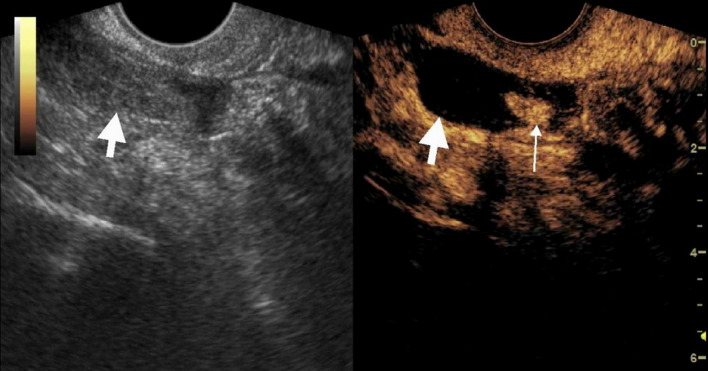

Results: A total of 21 patients were included: 19 with tEP, 1 with ovarian pregnancy, and 1 with intrauterine pregnancy. The sensitivity, specificity, and accuracy of transvaginal ultrasound (TVUS) for diagnosing tubal dilation were 15.8%, 100%, and 23.8%, respectively. For CEUS, these values were 94.7%, 100%, and 95.2%, respectively. Statistically significant differences were observed between CEUS and TVUS in sensitivity and accuracy (P = 0.000). The enhancement pattern of villous tissue was categorized as either circular or non-circular. Among the tEP cases, 2 exhibited circular enhancement and 17 showed non-circular enhancement. Based on positive β-HCG, absence of an intrauterine gestational sac, and sonographic visualization of a dilated fallopian tube containing either circular or non-circular enhancement internally, CEUS demonstrated high diagnostic accuracy for tEP diagnosis in cases with low β-HCG levels. CEUS correctly diagnosed 18 of 19 tEP cases. One tEP case was diagnosed as a mass of uncertain significance. The intrauterine pregnancy case was misdiagnosed as an EP. The ovarian pregnancy case was diagnosed as EP, though CEUS indicated a relatively high possibility of ovarian origin.

Conclusion: In conclusion, CEUS holds significant diagnostic value for tEP. It is particularly useful in diagnostically unclear cases and provides a more detailed assessment of the internal structure of adnexal masses.